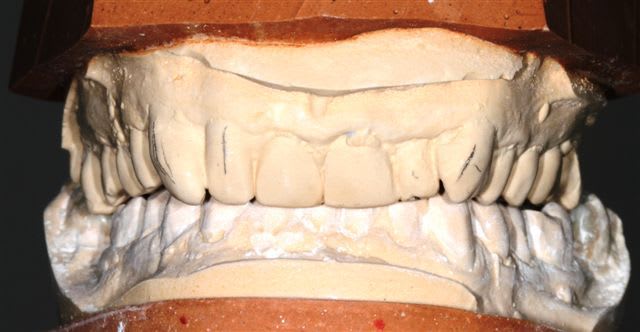

Postérieur bas (16/08)et haut (14/09) en place, essayage des Emax avec "cutback".

Pour la teinte la patiente exige B1, sans maquillage, elle n'a pas attendu 47 ans pour que ça ne soit pas Blanc de blanc, alors là dessus j'ai cédé.

Cas typique de patient refusant l'ortho avant la réhabilitation global, avec un résultat esthétique ....disons que j'aime pas, bon si la patiente est contente!

Moi en tout cas au prochain patient qui refuse l'ortho nécessaire avant la réhabilitation globale, je lui montre ce cas. Merci encore je pense que cela sera utile.

Peut-on encore à ce stade diminuer (fortement) le volume des canines, réaligner les faces vestibulaires des PM droites, augmenter le volumes des centrales et distaliser les latérales???

Une petite élongation coronaire sur 11 et 21 n'aurait pas été de refus si racine pas trop courte.

1) la patiente a une paralysie faciale (levre superieure gauche). Le fait que les canine-premolaires-molaires cote II soient plus longues que les incisives accentue ce probleme.

Je raccourcirais ttes les dents de 23 à 26 de 2mm.

2) Axe de 13 pas bon. trop de bombe vestibulaire. Peut etre que la dent n'est pas assez taillee. En tout cas je la trouve trop dominante dans le sourire.

09/10/2012 à 19h11

Les 2 canines sont effectivement très massives... Après tu fais avec les moyens que la patiente te donne, évidemment, mais là pour le coup je trouve pas ça très beau non plus.